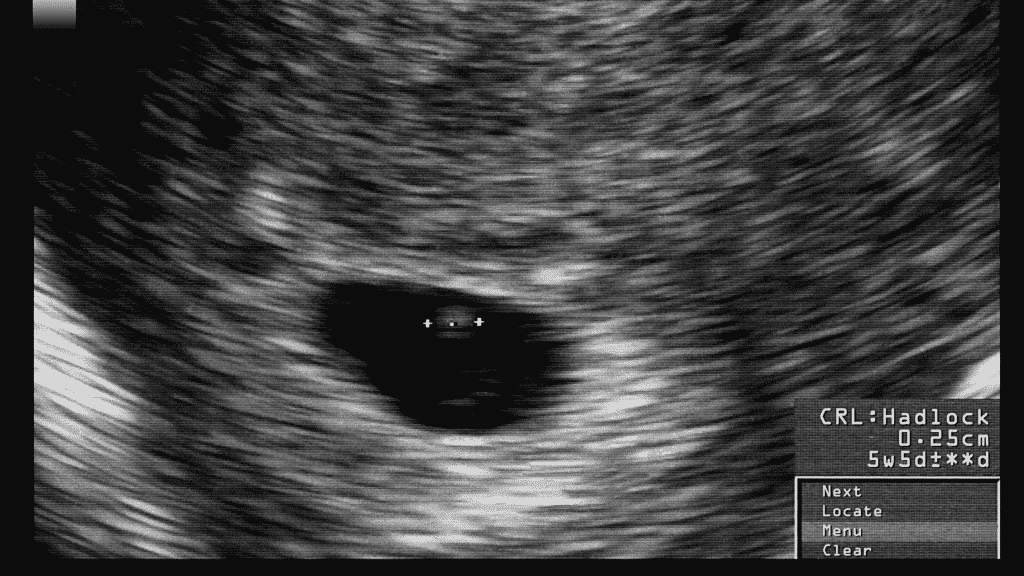

viewamiracle.comFirst Ultrasound Shows I’m 3 Weeks Behind | BabyCenter

viewamiracle.comFirst Ultrasound Shows I’m 3 Weeks Behind | BabyCenter

fetalmedicine.com3 Weeks Pregnant: All You Need To Know | MindTastik

fetalmedicine.com3 Weeks Pregnant: All You Need To Know | MindTastik